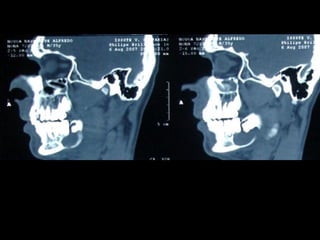

En el estudio radiográfico determinamos que el factor causal fué un foco séptico

dentario a nivel de segundo molar inferior izquierdo.